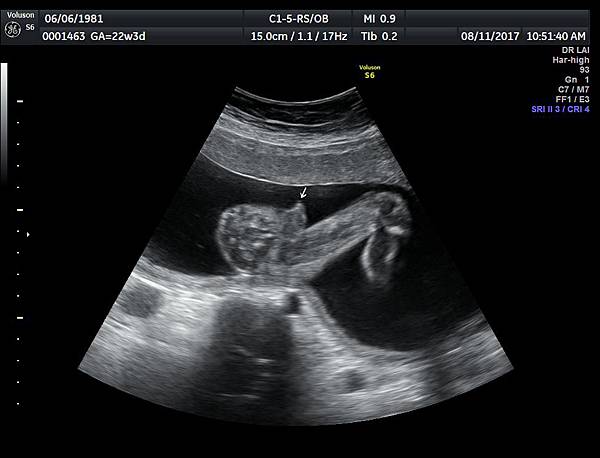

今天下午一位28歲第一胎的孕婦來診所做超音波檢查,之前他們一直認為懷的是女兒(檢查前資料顯示胎兒是女生);今天我的診斷胎兒是男生,但是懷疑有尿道下裂的問題(附圖 1~4),我的建議是抽羊水做染色體基因檢查,除了確定性別之外,也可以排除是否合併基因異常。

2018年3月的一位孕婦,產檢期間醫師也覺得比較像女生,羊水報告卻是男生,經過我的檢查,診斷是胎兒懷疑有尿道下裂(附圖 5.),產後證實是尿道下裂(附圖 6.7.)。

診斷尿道下裂常用的鬱金香sign(tulip sign)(附圖 10.11.),它的特徵就是龜頭陷入陰囊中間,胎兒如果是男生,一定要看到龜頭離開陰囊,這樣就沒有問題,每次遇到尿道下裂的個案時,我都會有一個感觸,男生如果能站著尿尿都要很感恩。